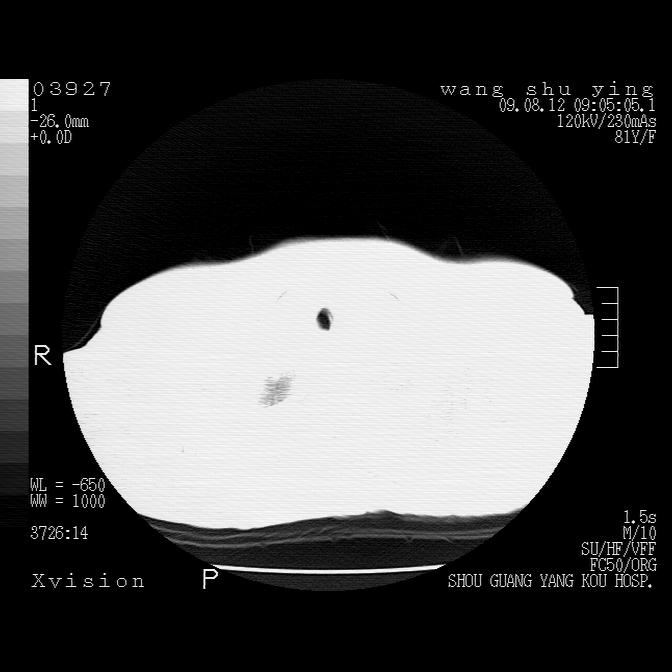

以下是引用帅河马在2009-8-12 12:59:00的发言:[br]两肺感染性病变伴双侧胸膜肥厚。[br]左侧甲状腺腺瘤不除外。[br]腹水+心包积液。[br][br][本贴已被 帅河马 于 2009-8-12 13:14:32 修改过]

以下是引用sdzyy在2009-8-12 18:17:00的发言:[br]两肺感染性病变伴双侧胸膜肥厚。[br]左侧甲状腺腺瘤不除外。[br]腹水+心包积液。[br]支持

以下是引用随光逐影在2009-8-12 19:42:00的发言:[br]1)两肺感染性病变伴双侧胸膜肥厚。2)不排除左侧甲状腺腺瘤。3)肝脏占位性病变;建议行进一步检查。